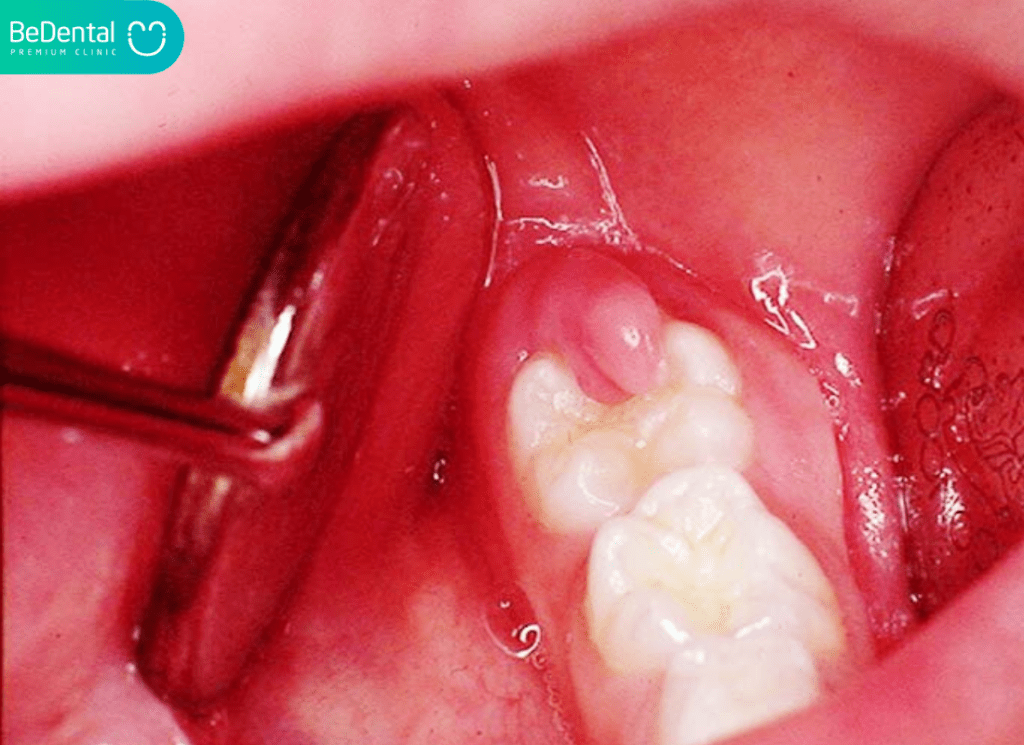

Răng khôn mọc lệch, mọc ngầm không chỉ gây ra những cơn đau nhức âm ỉ, khó chịu mà còn là “mầm mống” của nhiều biến chứng nguy hiểm như viêm lợi trùm, sâu răng số 7 hay u nang xương hàm. Chính vì vậy, hầu hết các trường hợp này đều được bác sĩ chỉ định can thiệp nhổ bỏ để bảo vệ sức khỏe răng miệng toàn diện.

Tuy nhiên, việc nhổ răng chỉ là bước khởi đầu; quá trình hồi phục có diễn ra suôn sẻ hay không phụ thuộc rất lớn vào chế độ chăm sóc tại nhà. Việc nắm vững các lưu ý sau khi nhổ răng khôn sẽ giúp bạn rút ngắn thời gian lành thương và tránh được những rủi ro không đáng có.